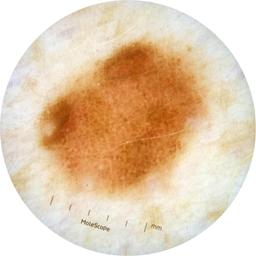

MEL-SELF - Dermoscopic

- Name: MEL-SELF - Dermoscopic

Description:

Dermoscopic lesion images (close-up views of benign and malignant lesions) from the MEL-SELF trial (the Melanoma Self Surveillance trial).